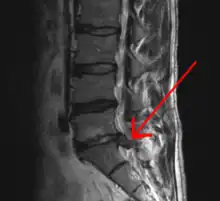

![]() |

![]() | |

The straight leg raise test can detect pain originating from a herniated disc. When warranted, imaging such as MRI can provide clear detail about disc related causes of back pain (L4–L5 disc herniation shown) | ||

Este indicată efectuarea unor radiografii în cazul existenței unor semnale de avertizare, simptome neurologice persistente care nu dispar sau dureri constante ori agravante.[8] În special, utilizarea timpurie a radiografiilor (IRM sau CT) este recomandată în cazul în care pacientul este suspectat de cancer, infecții sau sindromul cozii de cal.[8] Imagistica prin rezonanță magnetică (IRM) este ușor mai bună decât testele CT pentru a identifica bolile de coloană - cele două tehnologii sunt la fel de utile pentru a diagnostica stenoza spinală.[8] Numai câteva teste de diagnosticare fizică sunt utile.[8] Testul de elongație femurală iese aproape întotdeauna pozitiv la persoanele cu hernie de disc.[8] Discografia lombară stimulată poate fi utilă pentru a identifica un anumit disc care provoacă durere persoanelor cu niveluri ridicate cronice de durere lombară.[23] În mod similar, procedurile terapeutice, precum blocajele nervoase, pot fi folosite pentru a identifica o anumită sursă de durere.[8] Unele probe încurajează utilizarea injecțiilor în articulațiile fațetate, injecțiilor epidurale transforaminale și a injecțiilor sacroiliace ca metode de testare a diagnosticului.[8] Majoritatea celorlalte teste fizice, precum evaluarea scoliozei, slăbiciunea musculară sau wastingul muscular, precum și reflexele afectate au o utilitate redusă.[8]